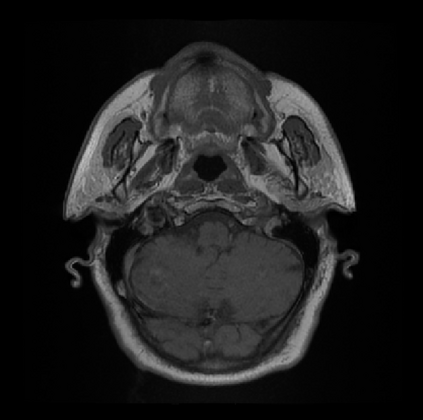

Organ at risk (OAR) segmentation is a critical process in radiotherapy treatment planning such as head and neck tumors. Nevertheless, in clinical practice, radiation oncologists predominantly perform OAR segmentations manually on CT scans. This manual process is highly time-consuming and expensive, limiting the number of patients who can receive timely radiotherapy. Additionally, CT scans offer lower soft-tissue contrast compared to MRI. Despite MRI providing superior soft-tissue visualization, its time-consuming nature makes it infeasible for real-time treatment planning. To address these challenges, we propose a method called SegReg, which utilizes Elastic Symmetric Normalization for registering MRI to perform OAR segmentation. SegReg outperforms the CT-only baseline by 16.78% in mDSC and 18.77% in mIoU, showing that it effectively combines the geometric accuracy of CT with the superior soft-tissue contrast of MRI, making accurate automated OAR segmentation for clinical practice become possible. See project website https://steve-zeyu-zhang.github.io/SegReg